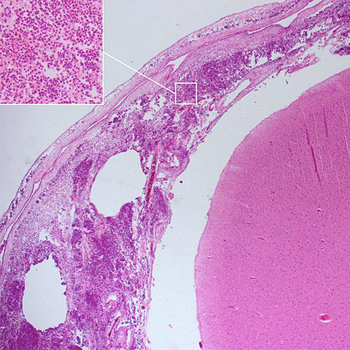

Los investigadores, liderados por la <a href="https://canal.ugr.es/noticia/cientificos-espanoles-demuestran-la-absorcion-intestinal-compuestos-bioactivos-del-romero-propiedades-anticancerigenas/" alt="Universidad de Granada" title="Universidad de Granada" target="blank">Universidad de Granada</a>, (UGR), han descubierto que varios compuestos bioactivos presentes en esta planta, <i>Rosmarinus officinalis</i>, efectivos frente al cáncer colorrectal, son absorbidos por el intestino delgado. El estudio ha sido publicado en <a href="https://www.sciencedirect.com/science/article/pii/S1756464617301639" alt="Journal of Functional Foods" title="Journal of Functional Foods" target="blank">Journal of Functional Foods</a>.